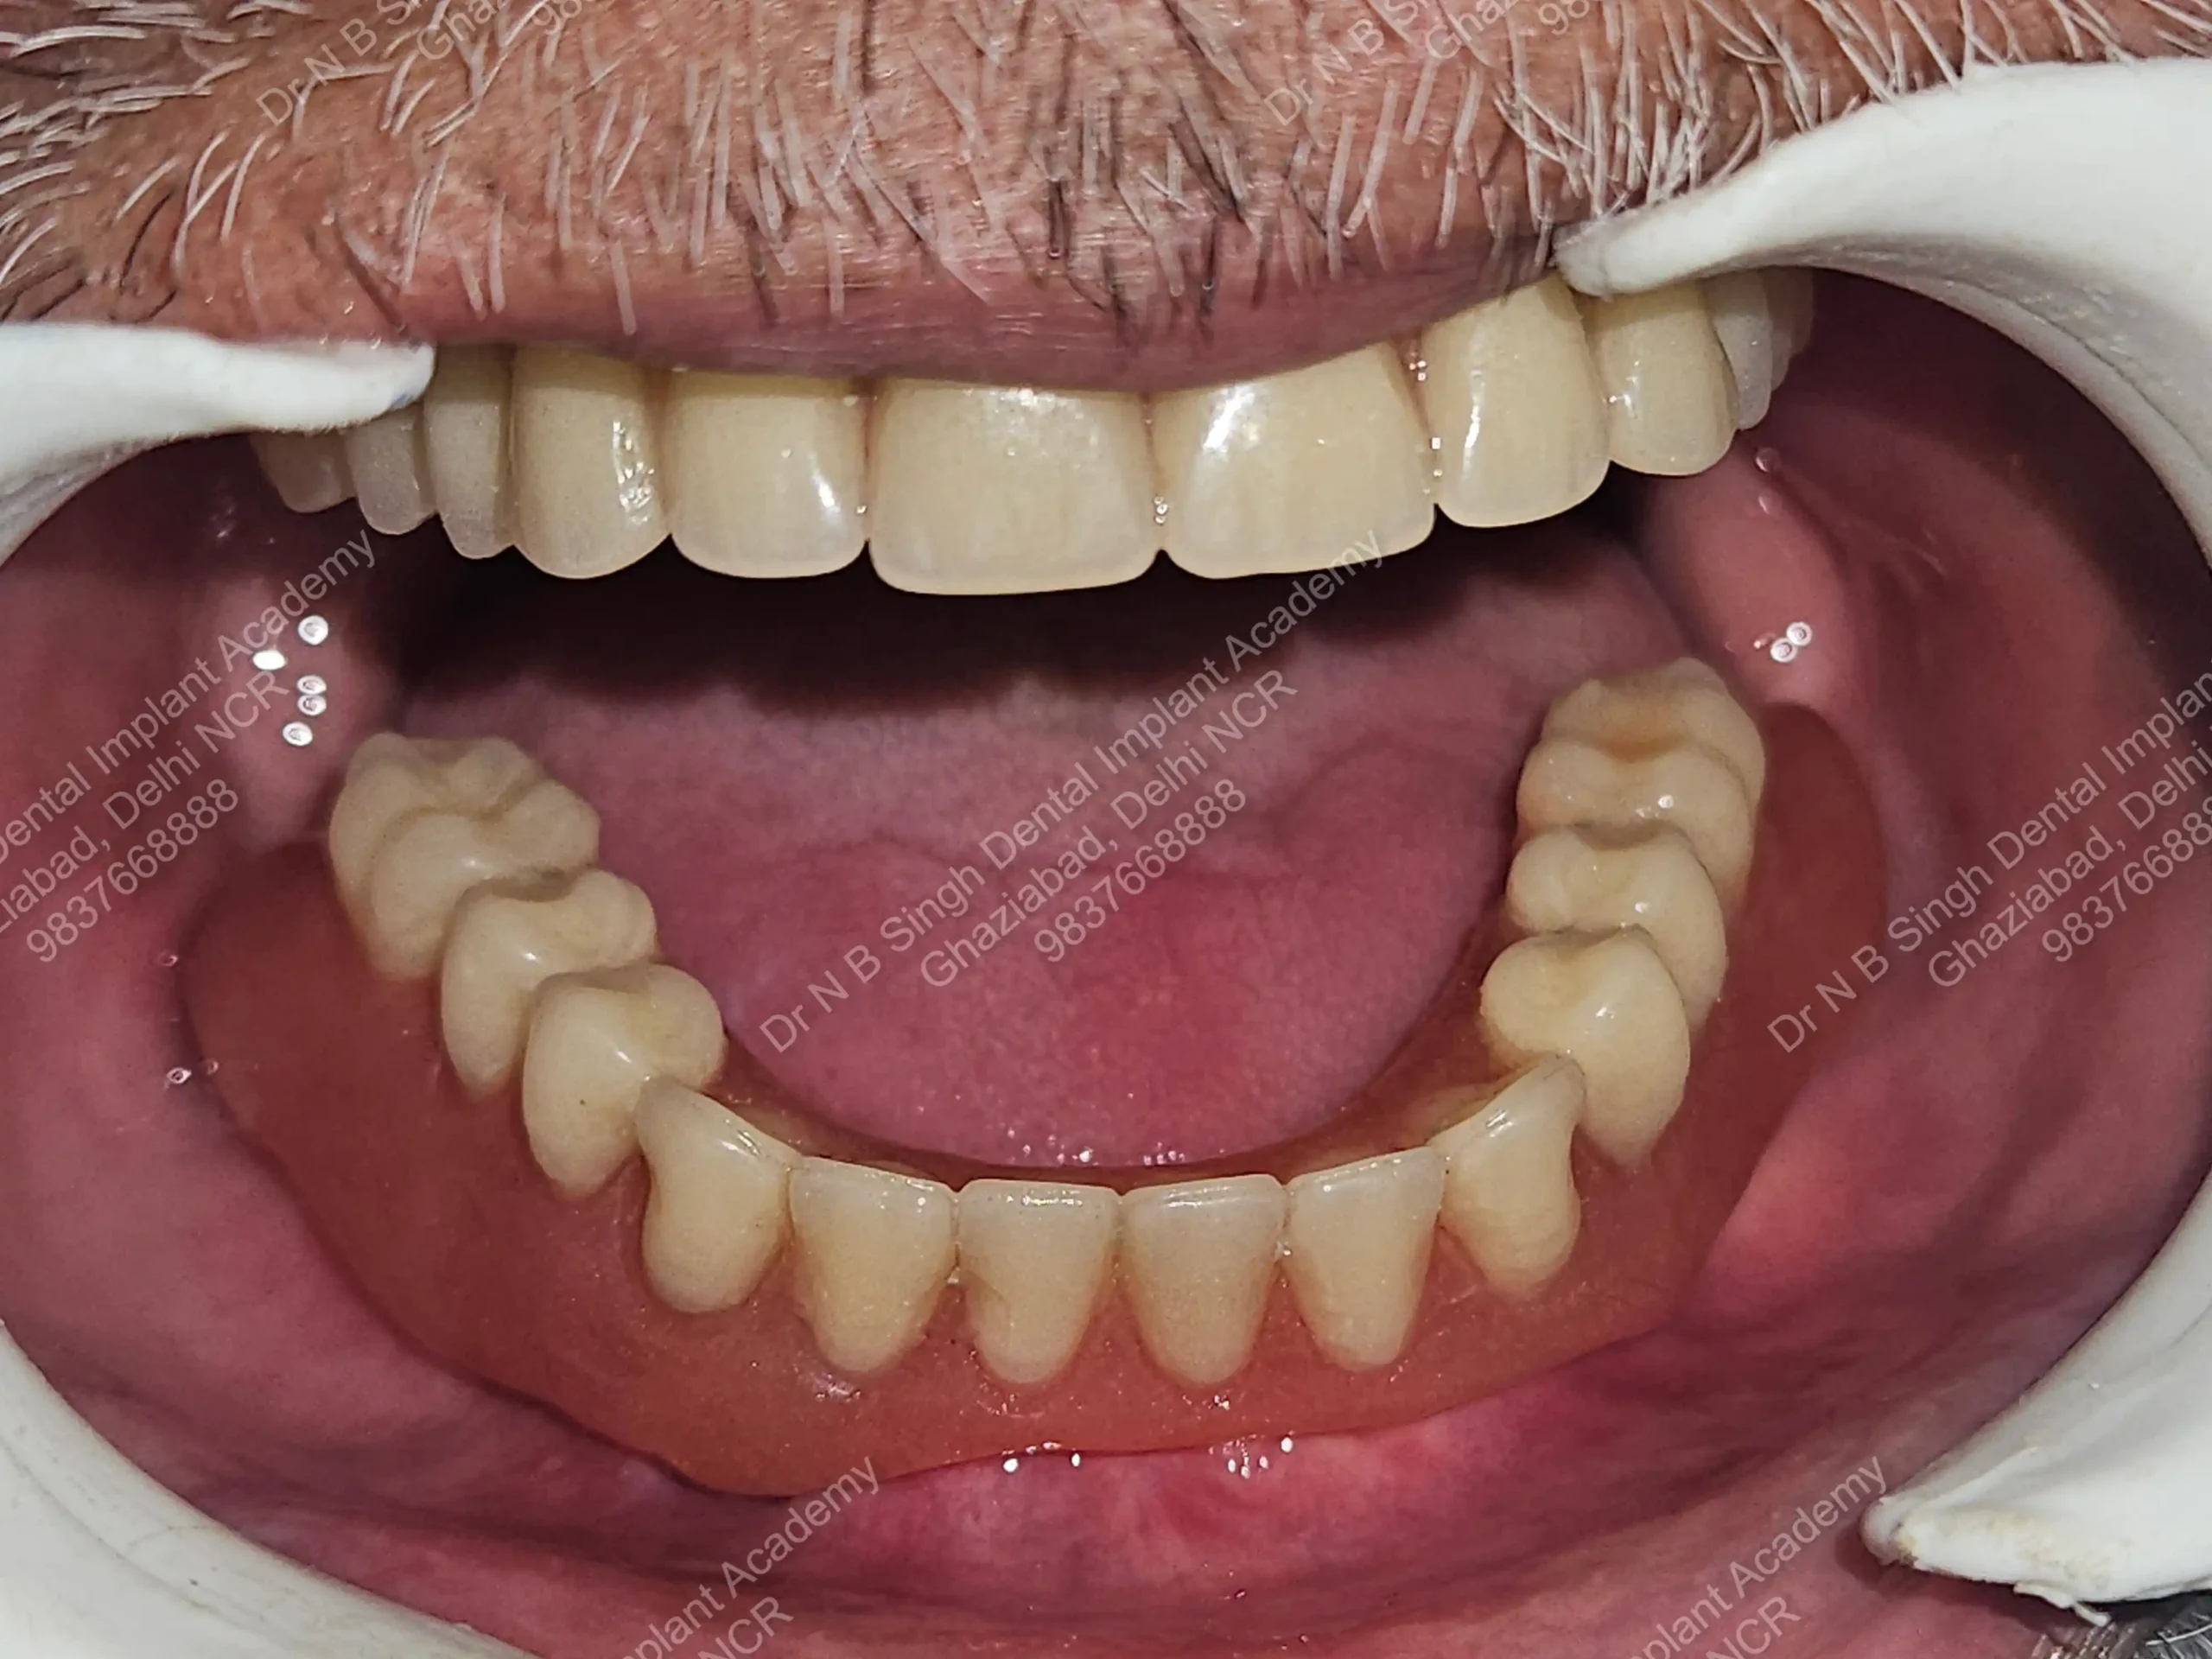

A008 Basal implants – af-qurs 1

Dr. N.B. Singh